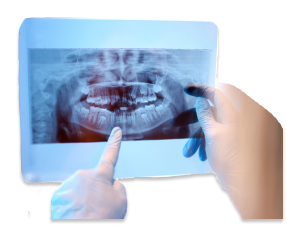

Our office uses the latest in technology so that we can provide you with the best care possible. We use a CT scanner to produce 3D images of your teeth, soft tissues, bone, and nerve pathways in just one scan. This helps us to effectively plan your treatment. We also have a digital impressions machine, which does not use the messy paste of traditional impressions. Since 2011, we have provided oral and maxillofacial surgery in Omaha, Nebraska, and the surrounding areas of Elkhorn, Blair, Bennington, Bellevue, Council Bluffs, Fremont, and Norfolk, Nebraska. We welcome you to contact Village Pointe Oral Surgery today to learn more about us and to schedule an appointment.